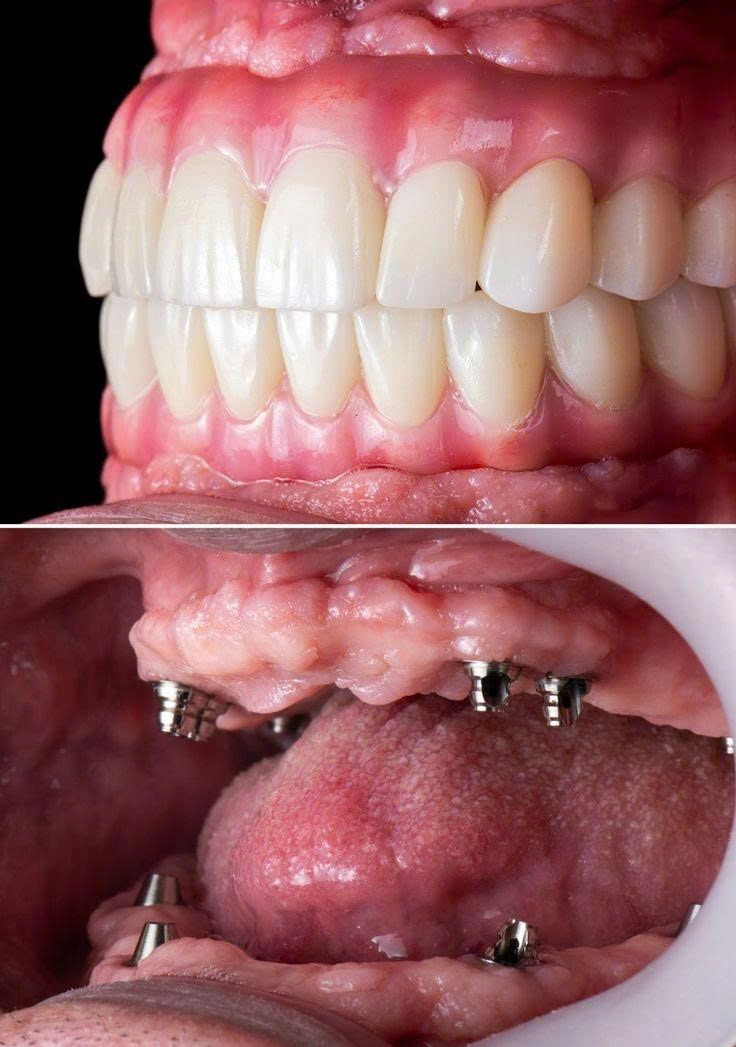

Cấu Tạo Của Một Chiếc Răng Implant

Răng Implant có cấu trúc gồm 3 phần chính, mô phỏng gần giống cấu tạo răng thật – giúp phục hồi cả chức năng ăn nhai lẫn thẩm mỹ.

Trụ Implant (Titanium)

Được cấy trực tiếp vào xương hàm, thay thế chân răng thật. Làm từ Titanium – vật liệu tương thích sinh học, tích hợp xương tự nhiên trong 3–6 tháng.

Khớp Nối Abutment

Là bộ phận kết nối giữa trụ Implant và mão sứ. Abutment truyền tải lực nhai từ mão sứ xuống trụ, đảm bảo độ vững chắc và ổn định lâu dài.

Mão Răng Sứ

Phần thân răng giả phía trên, được chế tác từ sứ cao cấp, hài hòa về màu sắc và hình dáng với răng thật. Tuổi thọ 15–20 năm, có thể thay mới dễ dàng.

Khám & Chụp CT 3D

Bác sĩ khám tổng quát, chụp phim Cone Beam CT 3D, lập kế hoạch điều trị chi tiết.

Cấy Trụ Implant

Gây tê vùng, đặt trụ chính xác bằng máng hướng dẫn phẫu thuật. Chỉ 20–30 phút.

Tái Khám & Cắt Chỉ

Sau 7–10 ngày, kiểm tra mức độ tích hợp xương và lành thương của trụ.

Lấy Dấu Răng Sứ

Sau 3 tháng, lấy dấu kỹ thuật số trên Implant, chọn màu sứ phù hợp với răng thật.

Gắn Mão Sứ Chính Thức

Gắn mão sứ, kiểm tra khớp cắn, hướng dẫn chăm sóc tại nhà. Hoàn thành!